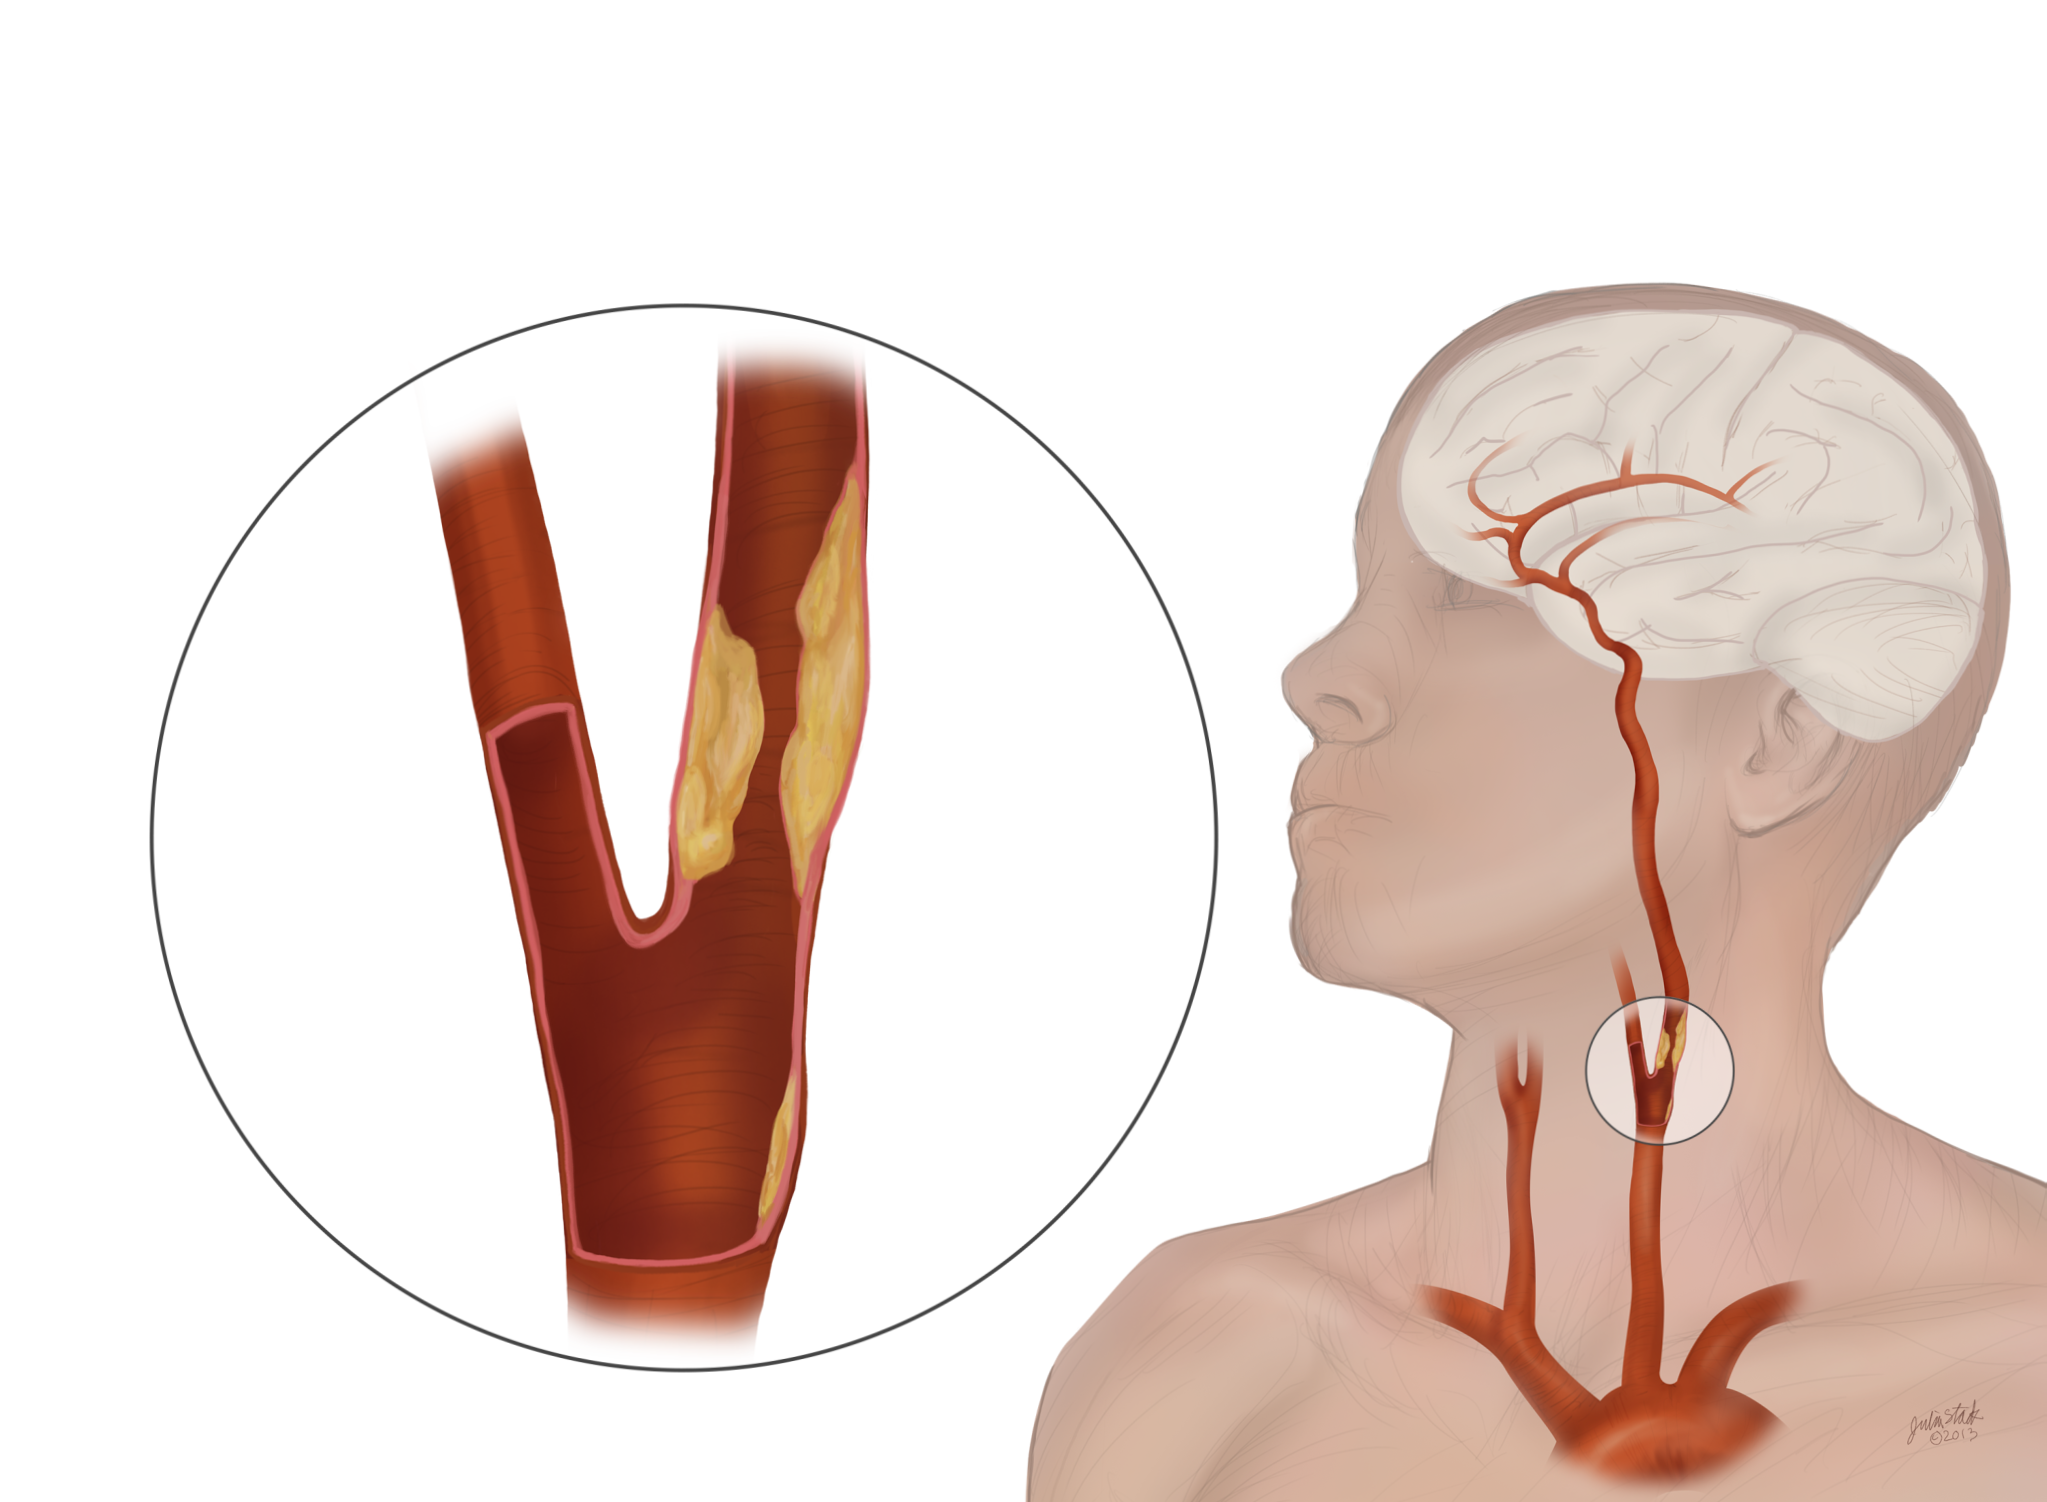

TCAR Procedure Savannah Vascular Institute

Carotid Artery Disease Stroke Victorian Vascular

Carotid Artery Disease CAD

Carotid Arteries Eye Patient

The Warning Signs Of Clogged Arteries Heart Blockage Clogged

Clogged Arteries Scientific Animations

Occluded Carotid Artery Carotisverengung Swiss Surgery